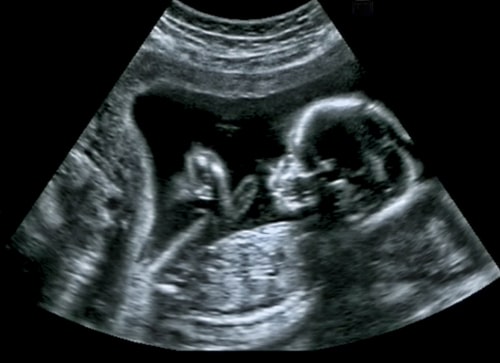

SURVEILLANCE DE LA GROSSESSE : EXAMENS MÉDICAUX La surveillance de la grossesse repose sur des examens cliniques, biologiques, échographiques. Quel suivi pour quelle grossesse ? Consulter le Document de synthèse de…

L’intérêt du Dépistage Anténatal Le dépistage anténatal permet la mise en évidence de malformations ou problèmes fœtaux pouvant conduire à des handicaps après la naissance. Il permet notamment la découverte…